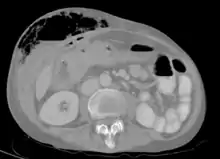

| Abdominal CT scan with right colocutaneous fistula and associated subcutaneous pneumatosis | |

In anatomy, a fistula (pl.: fistulas or fistulae /-li, -laɪ/; from Latin fistula, "tube, pipe") is an abnormal connection (i.e. tube) joining two hollow spaces (technically, two epithelialized surfaces), such as blood vessels, intestines, or other hollow organs to each other, often resulting in an abnormal flow of fluid from one space to the other.[2][3][4] An anal fistula connects the anal canal to the perianal skin. An anovaginal or rectovaginal fistula is a hole joining the anus or rectum to the vagina. A colovaginal fistula joins the space in the colon to that in the vagina. A urinary tract fistula is an abnormal opening in the urinary tract or an abnormal connection between the urinary tract and another organ. An abnormal communication (i.e. hole or tube) between the bladder and the uterus is called a vesicouterine fistula, while if it is between the bladder and the vagina it is known as a vesicovaginal fistula, and if between the urethra and the vagina: a urethrovaginal fistula. When occurring between two parts of the intestine, it is known as an enteroenteral fistula, between the small intestine and the skin as an enterocutaneous fistula, and between the colon and the skin as a colocutaneous fistula.[3]